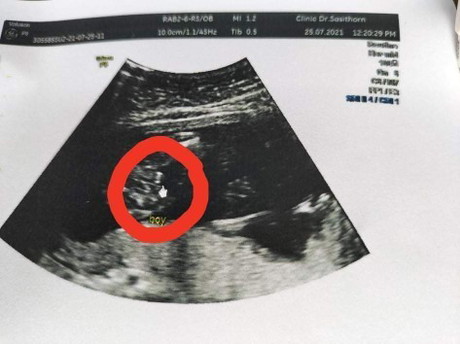

สอบถามหน่อยค่ะ ว่าเป็นหญิงรึชาย วงแดงหมอบอกเป็นชาย 18w วงเขียวหมอบอกเป็นหญิง 24w แม่นี่งงเลย 🤔